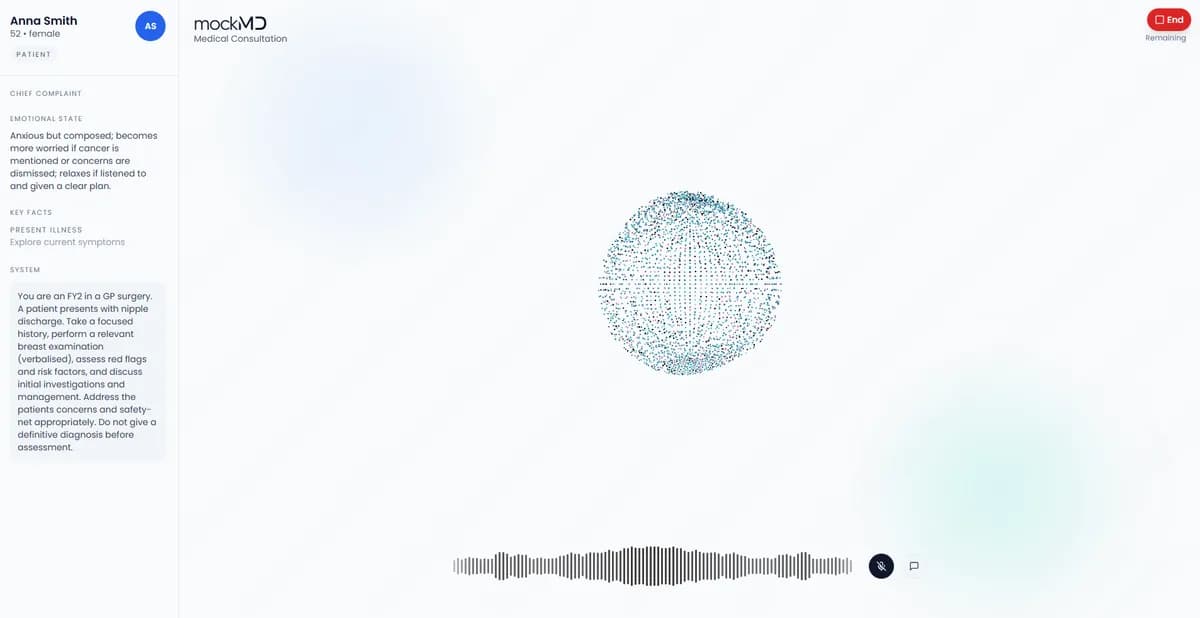

See the flow in one screen

The entire station experience including prep, conversation, and feedback feels like one seamless canvas.

Live patient dialogue

Run realistic, voice-first consultations where patient responses change based on your questioning style, structure, and clinical depth.